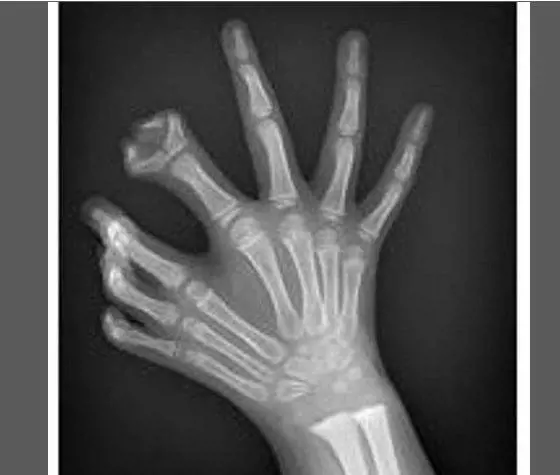

Pazze radiografie: gli oggetti che possono finire nel corpo umano

Oggetti bizzarri che hanno trovato la loro strada all'interno del corpo umano, e documentati grazie alle pazze radiografie raccolte dal dottor Frank Gaillard. Quest’ultimo ha fondato Radiopaedia.org, un sito collaborativo che raccoglie casi radiologici e articoli medici a tema.